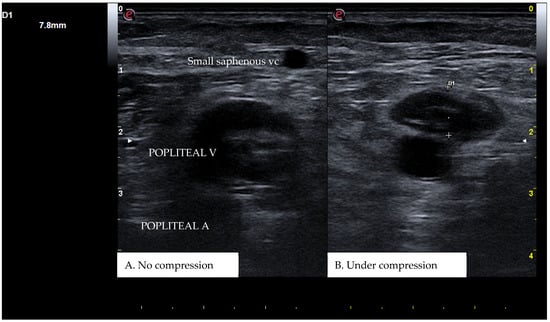

Figure 1. A real example of deep femoral vein thrombosis at the level of the upper left thigh (groin region). D1 shows the residual diameter of the non-compressible vein (i.e., the maximum diameter of the relative venous thrombus). D2 represents the venous diameter without compression.

CUS is a diagnostic technique primarily designed to find DVT by checking the veins’ compressibility with the principle that healthy veins are normally compressible and would collapse under the pressure of the ultrasonographic probe. In the case of the presence of a venous thrombus, the vessel would not be able to collapse under such pressure [8,9]. Linear high-frequency transducers are generally used for CUS as they best visualize leg veins [10]. The ultrasound machine settings must be adjusted carefully in order to limit possible operator-related bias. Important elements to be considered in this setting include gain, focus, and time-gain compensation. Gain adjustment regulates image brightness, focus optimization sharpens the image to the desired depth, and time-gain compensation enhances the visibility of subtle echoes, ensuring uniform image quality [10,11]. The transducer partially compresses the vein, which creates an echogenic response. In normal veins, this technique should fully compress the lumen [9]. However, with thrombosis present, the vein does not collapse enough, which causes a non-continuous echogenic line [12]. While the femoral veins are usually well identified in the groin and thigh areas, to facilitate better visibility of the popliteal veins, the patient may lie in a supine position with the leg slightly abducted to relax the muscles or, alternatively, in a prone position [9]. Real-time B-mode and Doppler imaging are both valuable tools in this process. B-mode imaging can find incomplete vein collapse during compression [13,14]. Doppler imaging can show the thrombus or find a complete lack of flow in the lumen [9]. As such, CUS for DVT diagnosis involves evaluating direct signs like the presence of a non-compressible echogenic line suggesting a thrombus, as well as indirect signs like changes in vein compressibility and thrombus echogenicity [6,7]. In addition, evaluation of flow patterns and flow response during augmentation maneuvers may refine the diagnostic examination, although their implementation requires more advanced training and skills than simple CUS [7]. Clinicians should assess a spectrum of veins, including the external iliac, common femoral, superficial and deep femoral, popliteal, tibial, peroneal, gastrocnemial, and soleal veins, as well as the junctions with the great and small saphenous veins, representing the superficial systems [15]. Challenges exist in visualizing the iliac veins, especially in obese patients, yet phasic flow in the femoral veins can be indicative of DVT status, particularly for excluding iliac vein thromboses [16]. This comprehensive approach is standard in differentiating healthy veins, which should collapse and enlarge with augmentation maneuvers, from those with thrombosis, which show impaired response to pressure and flow changes [12,17]. Figure 1, Figure 2, Figure 3 and Figure 4 show real examples of DVT affecting different sites of the lower limb deep venous system, diagnosed through a CUS modality.